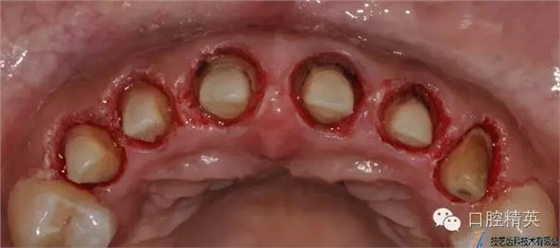

水激光切除牙齦